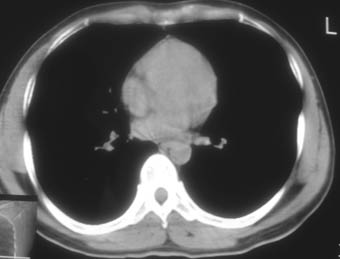

锁骨骨折复查,发现肺内高密度影,行ct检查。

男性,35岁,无任何感觉,无明显发热感冒病史。

纵隔窗!

右肺下叶背段斑片状阴影,边缘模糊,纵隔内未见肿大淋巴结,病人无发热及感冒史,要考虑浸润型肺结核,可结合ppd检查,或短期抗炎治疗复查。

右肺下叶背段长椭圆型病灶,边缘较规则,无明显分叶征、毛刺,远段未见阻塞征象,病灶较松散,纵隔窗明显小于肺窗,年龄35岁,支气管稍示变窄,纵隔内未见明显肿大淋巴结,这些都不支持肿瘤。病人无任何感觉,无明显发热感冒病史,首先考虑结核(也是结核好发部位),慢性炎症不能完全除外。